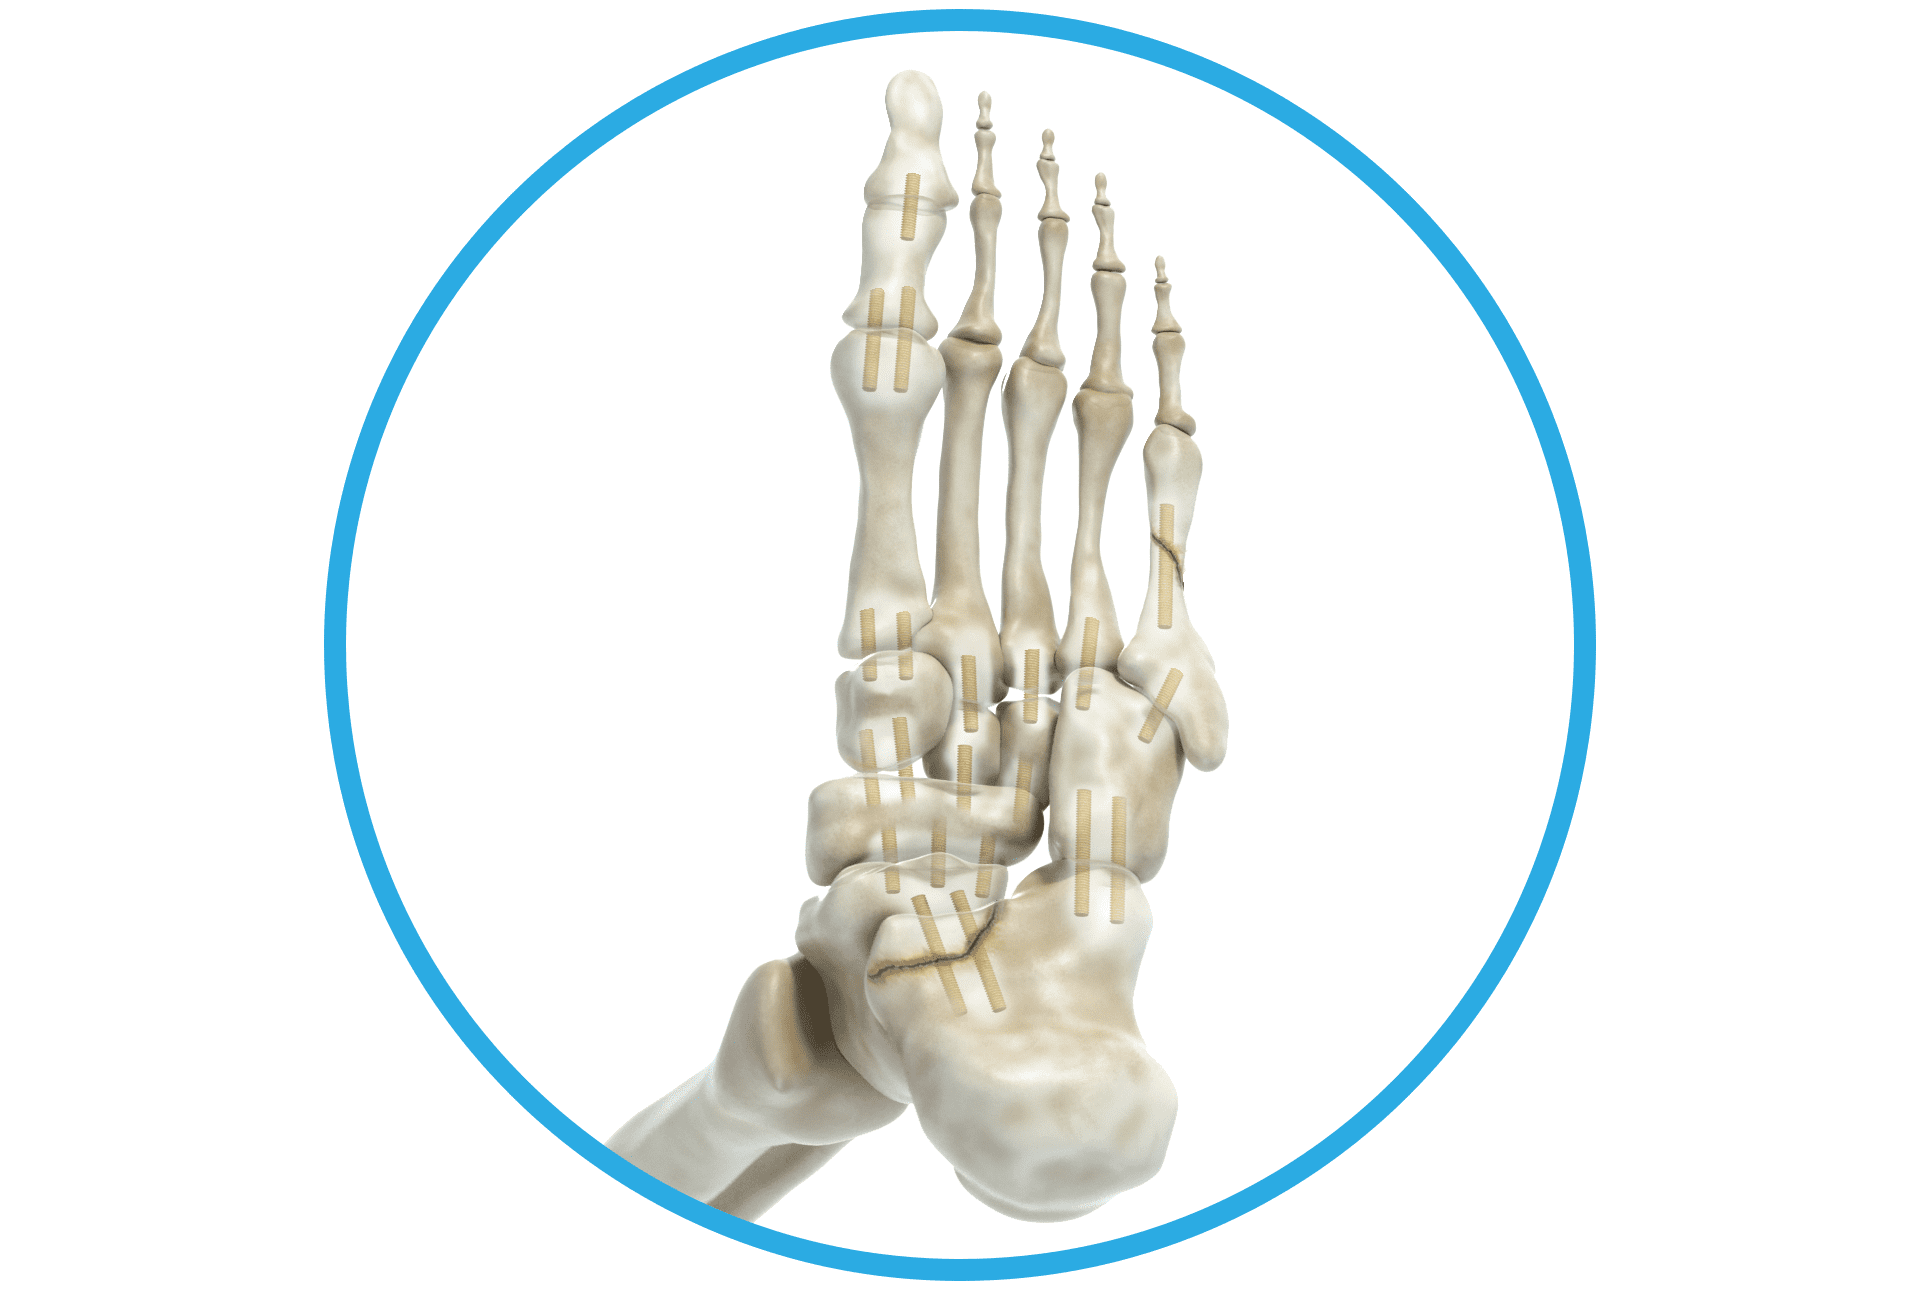

Als Shark Screw® Hero nützen Sie die natürlichen Vorteile intakter Havers-Kanäle und Co-Spaces in der Shark Screw®. Damit setzen Sie eine solide Knochenbrücke mit feinsten Kanälen und Co-Spaces über die und in welche Zellen wandern können. Dadurch wird primäre Knochenheilung zwischen Shark Screw® und Empfängerknochen sowie ein Remodeling der allogenen Knochenschraube möglich.1 Von diesen Eigenschaften profitieren Sie und Ihre Patienten vorzugsweise bei Arthrodesen, Frakturen, Pseudarthrosen und Umstellungen. Einen Auszug aus relevanten Studien zur Shark Screw® finden Sie hier.